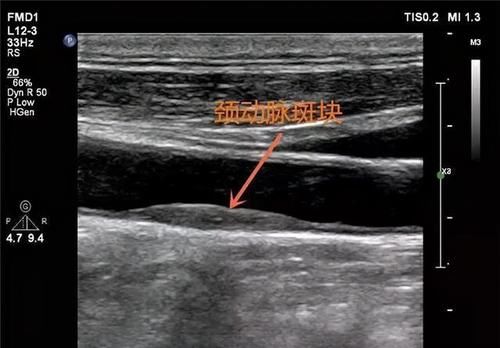

●颈动脉超声检查

动脉硬化和动脉硬化粥样都是由于血管病变,而导致各大动脉硬化,而颈部动脉属于人体大动脉之一,且连接肢体与头部血液流通及供应,位置独特、脂肪层较薄,因此若此处出现斑块,那么说明全身其他血管都有病变的可能。